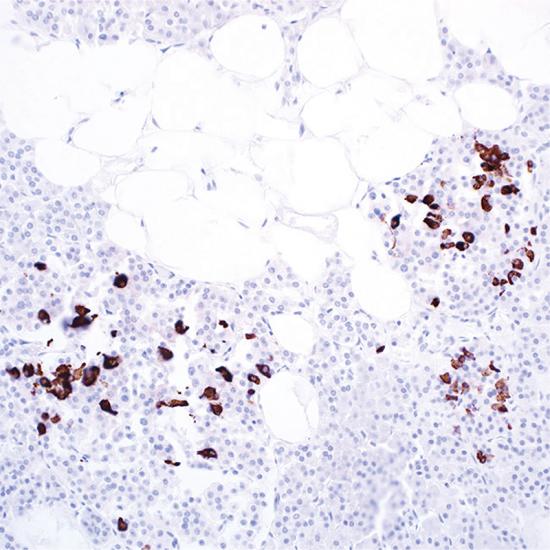

Somatostatin

Somatostatin抗體試劑(免疫組織化學(xué)) 閩廈械備20180282號

• 陽性部位:

細(xì)胞漿

• 陽性對照:

胰腺

生長抑素(Somatostain)是由116個氨基酸的大分子肽裂解而來的十四肽。主要作用是抑制垂體生長素(GH)的基礎(chǔ)分泌,也抑制腺垂體對多種刺激所引起的GH分泌反應(yīng)、包括運(yùn)動、進(jìn)食、應(yīng)激、低血糖等。